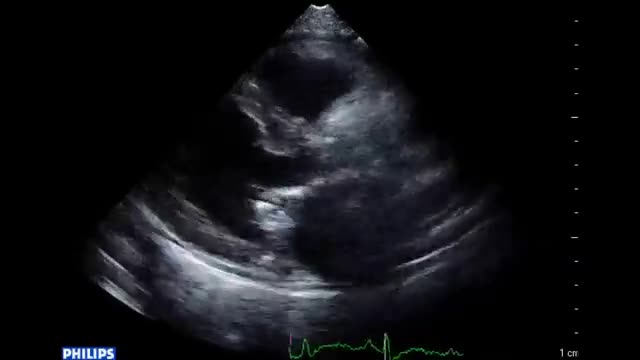

• 図4 心エコー図、手術所見 a

• 図5 心エコー、手術所見 a